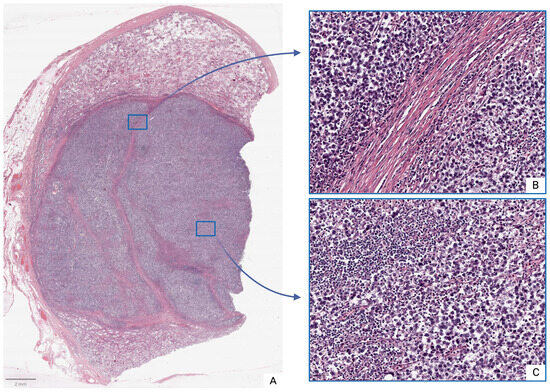

Moderate inflammatory infiltrates were observed in both tumor and peritumoral tissues, consisting of clusters of lymphocytes, plasma cells, and other immune-competent cells. Intercellular edema, microcyst formation, and foci of coagulative necrosis were also observed, particularly in the tunica albuginea, which frequently exhibited inflammatory cell infiltration (Figure 1).

Figure 1. Seminoma, subgroup Ib—pT2: (A)—histoscan; (B)—stroma; (C)—tumor. Staining: hematoxylin and eosin, magnification ×200.